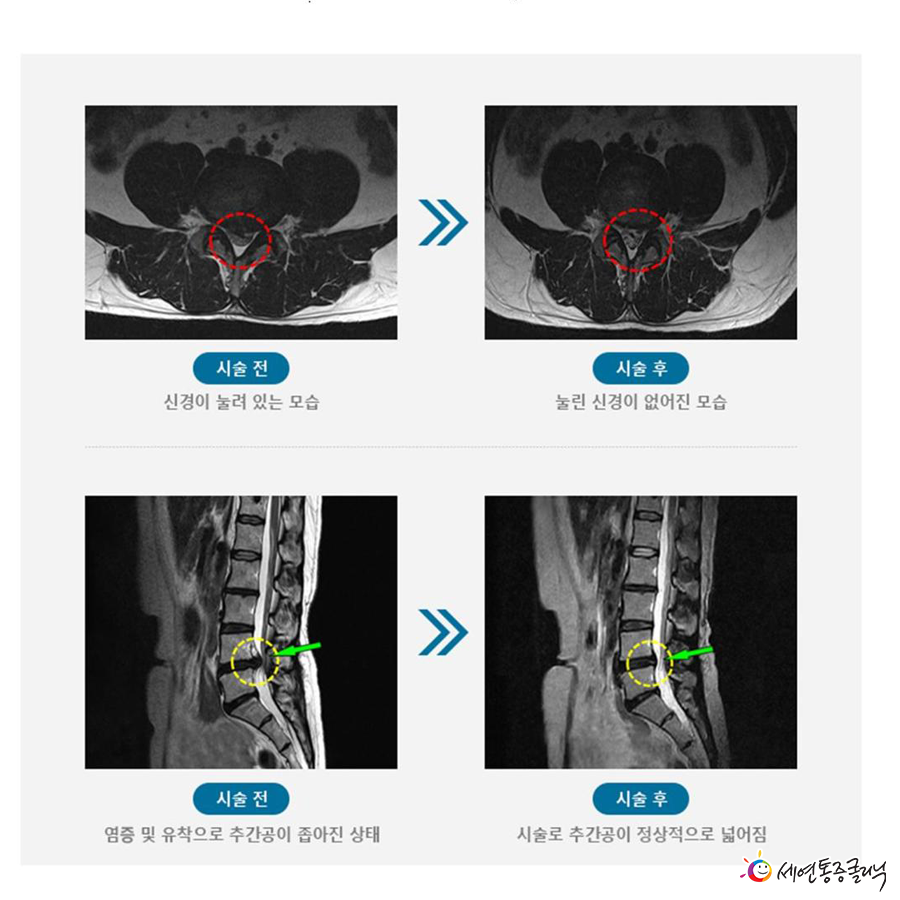

추간공에 염증이 발생할 경우, 주변 신경 유착이 심해지고 인대가 두꺼워져 추간공을 좁아지게 만드는데, 이 경우 ‘추간공확장술’을 실시합니다.

추간공확장술이란 신경이 압박된 부분의 인대를 긁어내 공간을 넓혀 신경이 지나가는 통로를 확보해 좁아진 추간공의 염증을 제거하는 비수술 치료 방법인데요.

꼬리뼈가 아닌 옆구리 쪽으로 특수 키트를 삽입해 추간공에 접근하는 방식으로, 퇴화된 인대를 긁어내 좁아진(막힌) 추간공을 넓혀주는(뚫어주는) 것입니다.